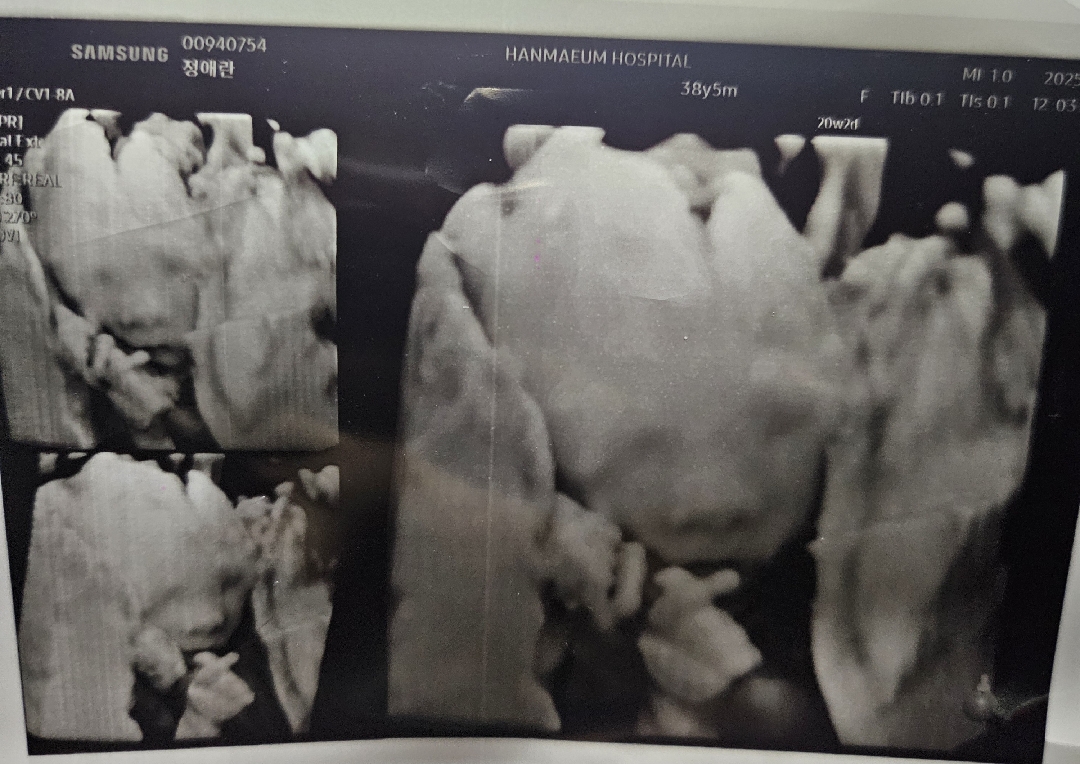

둘째,노산이라 걱정 많았는데

20주 입체초음파 보고왔어요 첫째때없던 입덧도 심하고 경부길이 짧아 맥수술도 하고 노산이라 니프티 검사에.. 걱정이 많았던 둘째네요 ㅎㅎ 초음파때 걱정말라고 보내는건지 손가락 하트에 마음이 놓이네요 ㅎㅎ 주수에 따라 임신증상이 나날이 늘어나지만 모두 힘내보아요!!!